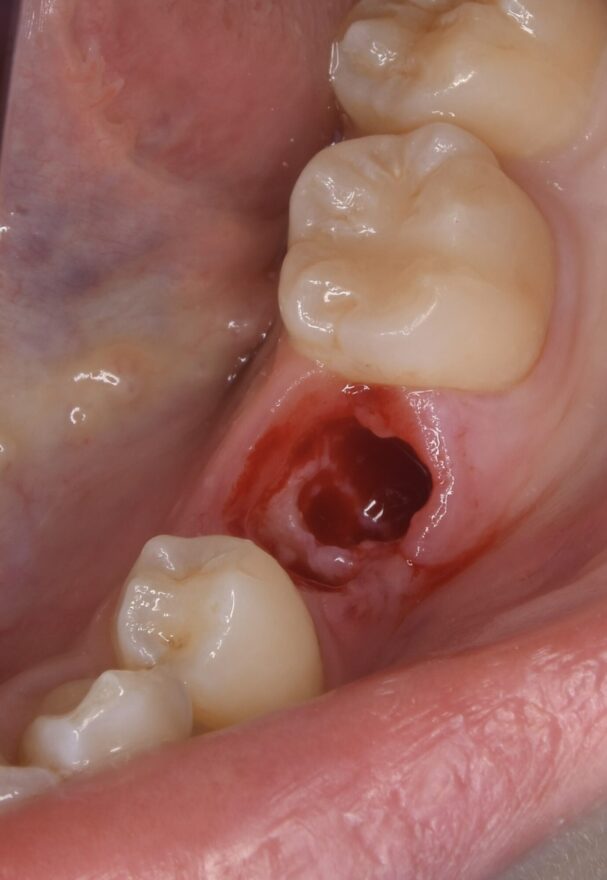

①乳歯を抜歯してのインプラント埋入。

インプラント治療の口腔内写真

ここまでのオペ時間はわずか10分。

もちろん痛みと腫れもありません。